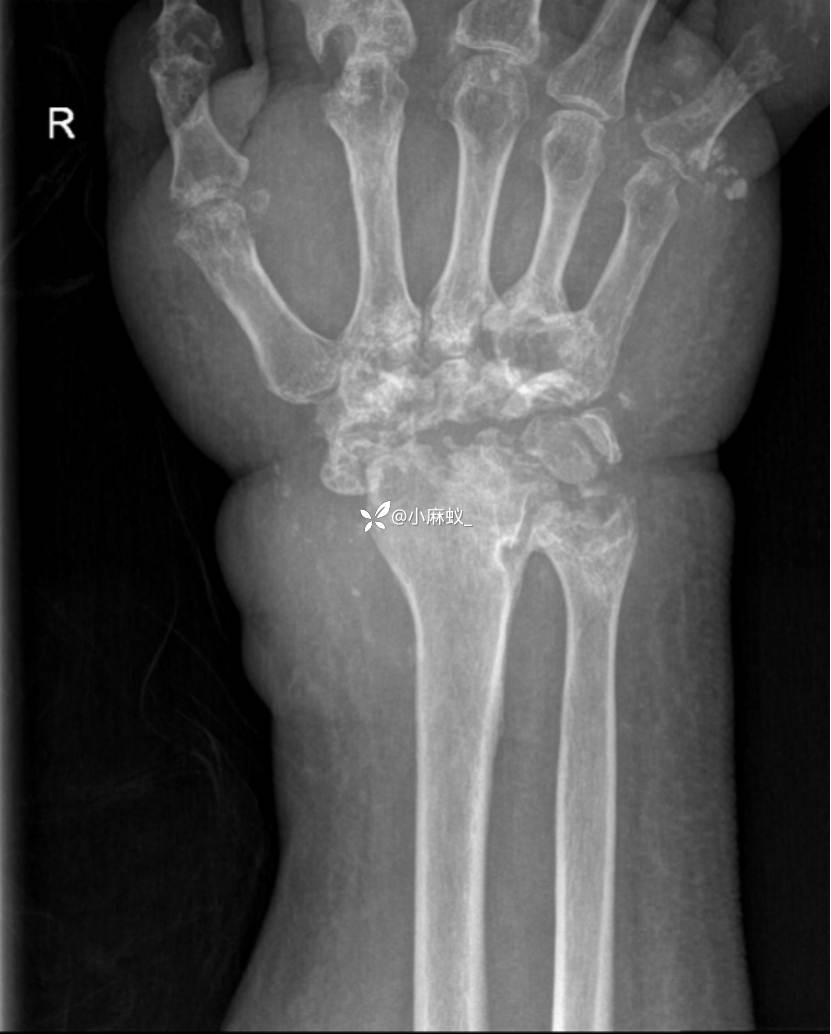

x线检查如下